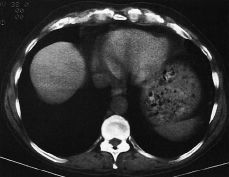

Policondritis recidivante: hallazgos en la TC

Recurrent polychondritis: CT findings

María Sánchez, María Martínez, María Isabel Padín, Félix Serrano